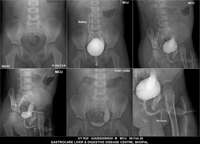

Section: URETHROGRAM Total: 95 images

BaM Enteroclysis Loopogram BaE Fistulogram Urethrogram HSG